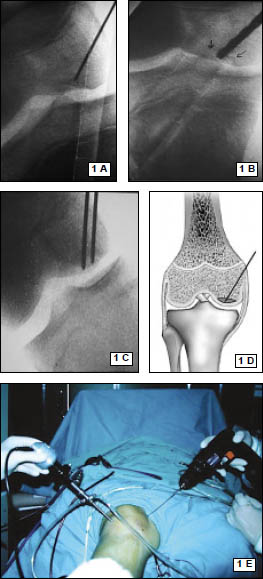

Rx con incidencias de frente y perfil de rodilla. (Fig. 1)

Figura 1: Rx perfil, rótula alta, hallazgo: encondroma de fémur distal.

Se realiza un mini abordaje anterior de rodilla 2 cm proximal al polo inferior de la rótula y 3 cm distal al mismo, luego se realiza la esqueletización del polo patelar distal cruentándolo a la demanda. Mediante dicho gesto se reconoce la superficie ósea permitiendo la implantación precisa de los arpones, centralizándolos en plena masa esquelética, se colocan en forma paralela 2 anclajes óseos de 3.5 mm (Arthrex). (Fig. 3 y 4)

Figura 3: Visión intraoperatoria de la lesión del tendón patelar, colocación de 2 arpones paralelos

Se realizaron radiografías de control en el postoperatorio inmediato. (Figs. 6, 7)